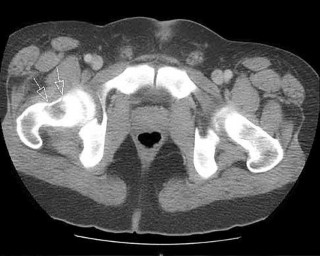

A 32-year-old male is brought to the trauma bay in hemorrhagic shock after a motorcycle crash. An anteroposterior radiograph of the pelvis demonstrates an APC-III injury. A pelvic binder is applied. To maximize reduction of the pelvic volume, at what anatomical landmark should the binder be centered?

Correct Answer: Greater trochanters

Explanation:

Pelvic binders should be centered over the greater trochanters to effectively close the pelvic ring and reduce pelvic volume. Placement over the iliac crests or ASIS can paradoxically widen the true pelvis or fail to achieve adequate reduction in an open-book pelvic injury.